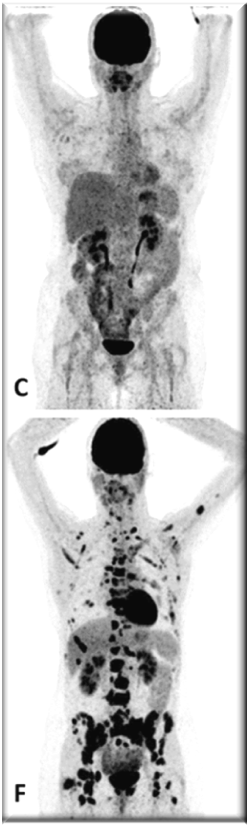

PET images of two patients with metastatic invasive lobular carcinoma responding (A-C) and not responding (D-F) to palbociclib + letrozole

Adapted with permission from Boers, J., et al. European Journal of Cancer. 2020; 126: 11-20

Upper row responder: (A) Baseline [18F]FDG-PET shows pathological uptake in axillary lymph nodes (right side) and in nearly all vertebrae and pelvic bones. (B) Baseline [18F]FES-PET with pathological ER expression in the axial skeleton (vertebrae, pelvic bones, proximal humeri and femora) and in axillar lymph nodes. (C) [18F]FDG-PET after 8 weeks shows almost complete metabolic response. The patient has been on treatment for more than 70 weeks.

Lower row non-responder: (D) Baseline [18F]FDG-PET shows pathological uptake in multiple skeletal lesions. (E) Baseline [18F]FES-PET with only some increased ER expression in thoracic vertebrae. (F) [18F]FDG-PET after 8 weeks shows no metabolic response, with some increase in the pathologic uptake in the multiple skeletal lesions.